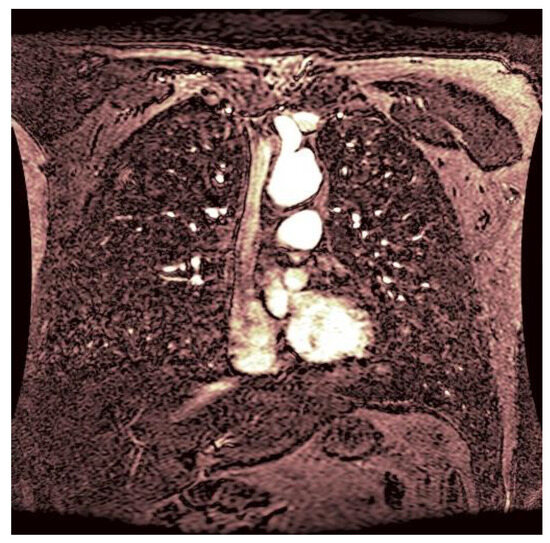

As statistical data have less relevance for life sciences, we add graphical displays of the studied angiograms. Surprisingly, even a simple denoising procedure can help reduce unwanted artifacts, as can be observed when comparing the angiogram E1154S7I064 (shown in Figure 5) with the result obtained by denoising it with the CLAHE method already described (shown in Figure 6). The corresponding image obtained by the wavelet-based CE method (shown in Figure 7) better outlines the biological features, making visible some details that cannot be observed in the original image (Figure 5), and allows us to take into consideration relinquishing contrast substances (a fact with multiple benefits for newborns and children). A visual comparison of CLAHE and wavelet-based CE method results in the performance obtained for this angiogram can be made with the images in Figure 8. It can be noticed that the original image is too dark to observe all the significant medical details and that the result of CLAHE is too luminous and can mask medical features. The same remarks concerning the advantages of the wavelet-based CE methods can be made upon a visual analysis of the original angiograms and the corresponding results shown in Figure 9, Figure 10, Figure 11 and Figure 12.

Figure 5. Original angiogram E1154S7I064. Despite the use of contrast substances (gadolinium contrast enhancement), the visibility is reduced.

Figure 6. The image was obtained by denoising the angiogram E1154S7I064 using the CLAHE method. The contrast is already improved, but the whole areas of the image are too luminous, details might escape.

Figure 7. The result of the wavelet-based CE method applied to the angiogram E1154S7I064 with visible physiological features to improve diagnosis.